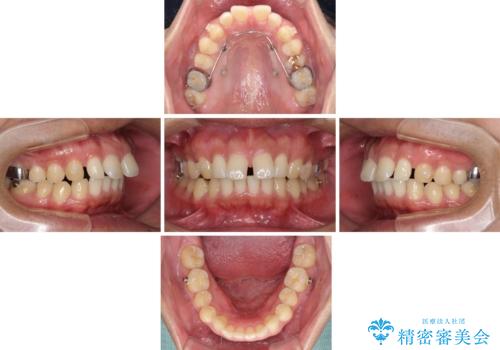

- 上顎前歯の突出感とすきっ歯を気にして来院された患者様です。

奥歯の咬み合わせを見ると、下顎に対して上顎が前方に位置していたため、補助装置により上顎歯列全体を後方に移動させ、その後インビザラインにて歯列全体を整えることとしました。

インビザライン開始前に奥歯の咬み合わせを変える補助装置は幾つかあります。

咬み合わせの強さや下顎の歯列の状態などによって、最適な補助装置を選択しています。

インビザライン単独で咬み合わせを改善することもできますが、治しきれない可能性が高いため、事前に補助装置で治しておくことは、治療の仕上がりの点で非常に重要となります。